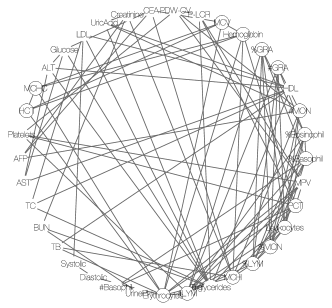

As already briefly commented in Section 1, graphical models may be also employed for finding hidden structures of the symptoms. We run a birth-death MCMC algorithm (available in the R package BDgraph, Mohammadi & Wit, 2015) for 50,000 iterations to learn a Bayesian graphical model. A point estimate is shown in Figure 8(d). Symptoms that form cliques of size greater than 3 are marked by circles. Some of the findings are consistent with those by the DFA. As an illustration, the clique of TC, triglycerides, LDL and HDL is very similar to latent disease 1 in Figure 8(a). However, although graphical models can find latent patterns that are not immediately obvious in the correlation structure (Figure 1a), like SLFM, it lacks inference on patient-disease relationships. Moreover, identifying cliques or other graph summaries as disease is an arbitrary choice.